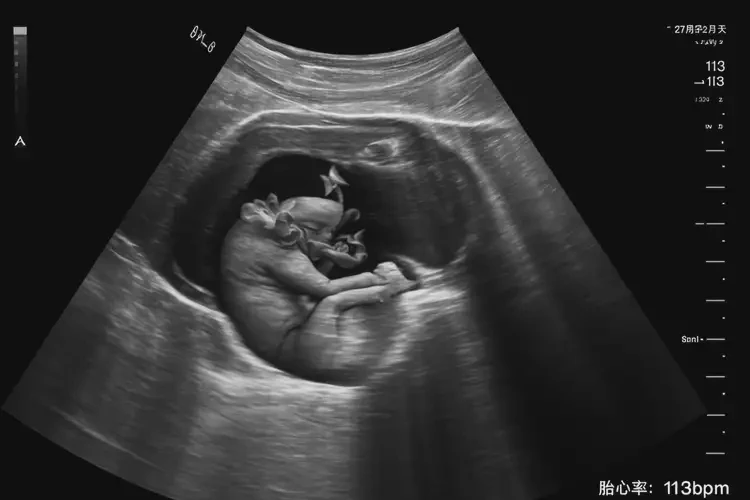

孕27周2天胎心113正常嗎

胎心113次/分鐘在孕27周2天屬于偏低范圍。

胎心率是指胎兒心臟每分鐘跳動(dòng)的次數(shù),正常情況下,胎心率在120-160次/分鐘之間。在孕27周2天時(shí),胎心率為113次/分鐘,低于正常范圍的下限,可能存在一些潛在問題。以下是對(duì)這一情況的詳細(xì)分析:

孕27周2天胎心113正常嗎(圖1)